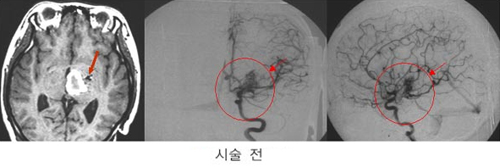

³úµ¿Á¤¸Æ

񃀁

³ú

±íÀº °÷¿¡ À§Ä¡ÇÏ¿© ³úÃâÇ÷À» ÀÏÀ¸Å² 17¼¼

¿©ÀÚȯÀÚÀÇ MRI ¹× ³úÇ÷°üÃÔ¿µ¼ú »çÁø.

³úÀÇ

±íÀº °÷¿¡ ³úµ¿Á¤¸Æ±âÇüÀÌ À§Ä¡ÇÏ¿© ¼ö¼úÀû

Ä¡·á°¡ ºÒ°¡´ÉÇÏ¿´À¸³ª °¨¸¶³ªÀÌÇÁ ½Ã¼ú

ÈÄ 24°³¿ù°¿¡ ¸ðµÎ ¿ÏÄ¡µÇ¾ú´Ù